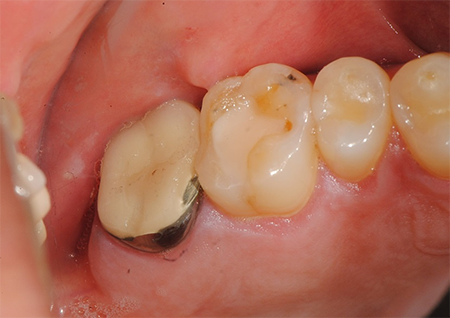

2차 충치로 넘어갔을 때의 치료 방법

인레이

충치로 인한 치아 손상이 넓은 경우 시행하는 치료입니다. 충치가 심하거나 기존 치료가 실패했을 때 금, 세라믹, 레진 등의 재료를 이용하여 수복물을 만들고 부착하는 치료입니다.

골드 인레이

생체친화성이 뛰어난 금 소재로 제작되어 내구성과 적합성이 우수하며, 어금니 부위에 적합한 인레이입니다.